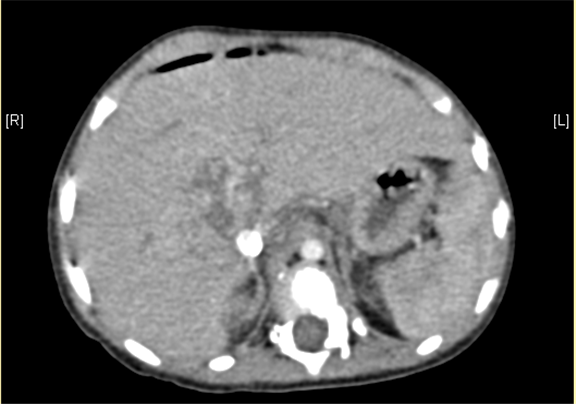

上腹部增强CT提示肝门处占位性病变,考虑腹膜后肿瘤可能性大,畸胎瘤? AFP 11.38ng/ml

术前CT检查:

动脉期

静脉期

平衡期